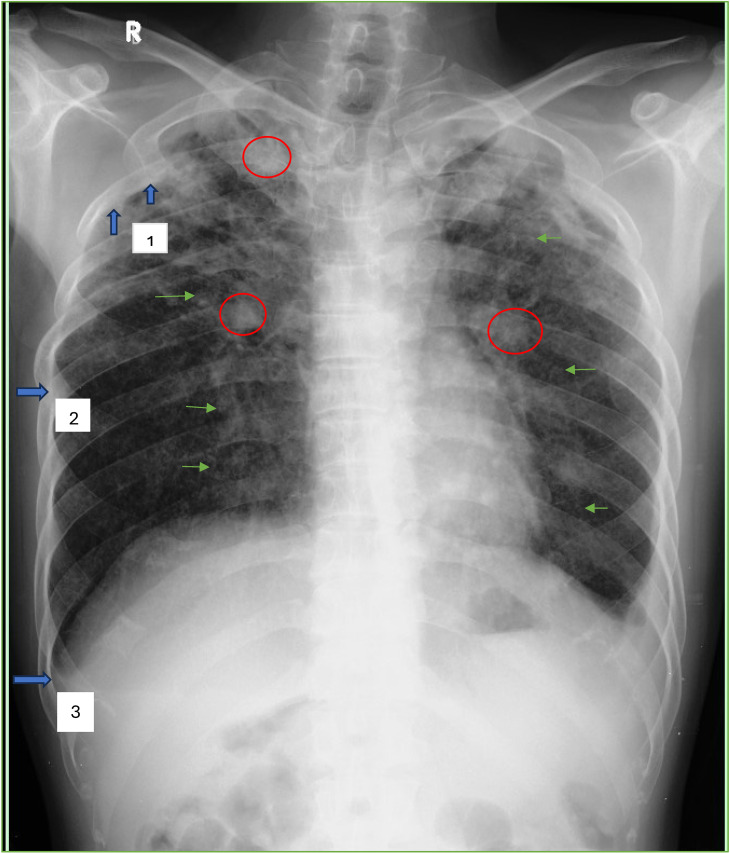

Methods: A hospital-based study in West Java among 148 MDR-TB patients (case) and 164 drug-sensitive/DS-TB patients (control) was conducted. Chest x-rays were evaluated by two radiologists and one NIOSH B reader according to the ILO Classification. Face-to-face interviews were conducted using structured questionnaires to collect patients' information, including the task of drug supervisor.

Results: Findings indicate that supportive drug supervisor reduces the risk of developing MDR-TB, but silicosis showed no significant association. Nevertheless, in this study we found that 17 cases (5.4%) had silico-tuberculosis mostly exhibited as ILO profusion 3; predominated by q shape, 52.9% with large opacities and dominated by size A. Other factors significantly associated with the risk of developing MDR-TB were marital status, low income, longer traveling time to hospital, unsuccessful previous treatment and suffering drug side effects.